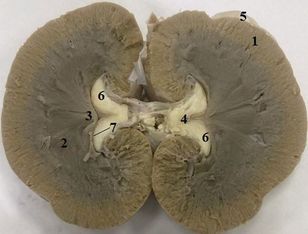

Почки собаки гладкие однососочковые, бобовидные, короткие, толстые, сосочек гребневидный (рис. 37). Почечных пирамид 12–17.

Рис. 37. Почка собаки

Рисунок 37 – Почка собаки:

1 – корковое вещество; 2 – пирамида мозгового вещества; 3 – почечный сосочек; 4 – лоханка почки; 5 – капсула; 6 – жировая ткань (в синусе); 7 – почечный гребень (Распутина О.В.. 2023)

Почечная лоханка у переднего и заднего концов почки в виде 5–6 мешковидных выпячиваний (recessus pelvis) вдается в паренхиму органа, где они вместе с кровеносными сосудами располагаются между почечными пирамидами. Обе почки расположены в поясничной области (1–4-й позвонки).

Особенности! У собак в почках нет чашечек.